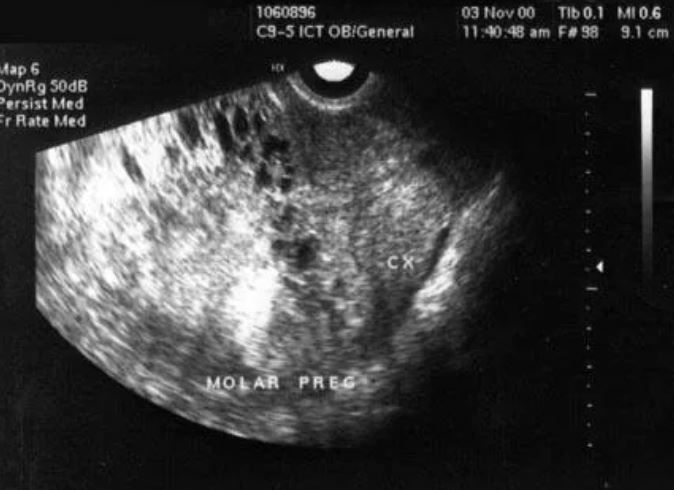

Медицина и диагностика: Инвазивный пузырный занос на УЗИ